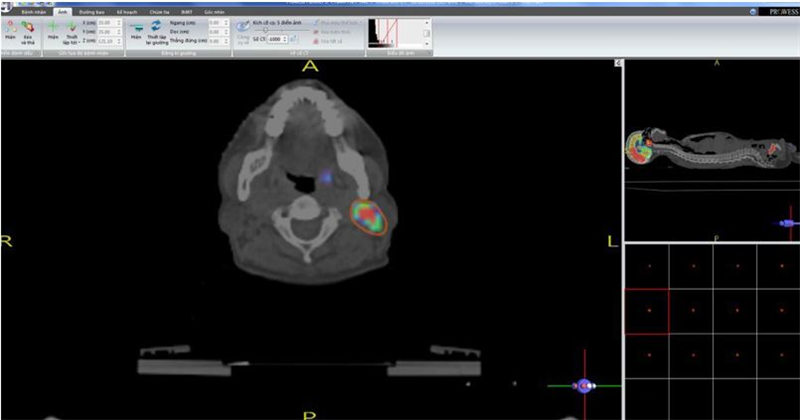

Tại Trung tâm Y học hạt nhân và Ung bướu Bệnh viện Bạch Mai lần đầu tiên tại Việt Nam ứng dụng chụp PET/CT mô phỏng và lập kế hoạch xạ trị cho các bệnh nhân ung thư các loại trong đó có ung thư vòm họng từ năm 2009. Đến nay có hàng trăm bệnh nhân được điều trị thành công với kỹ thuật này. Hiện tại chúng tôi đã có được phần mềm lập kế hoạch xạ trị 3D và IMRT trên hình ảnh CT mô phỏng và PET/CT mô phỏng bằng tiếng Việt, tạo thuận lợi cho các nhà xạ trị lập kế hoạch tốt hơn (hình 4 - 10)

Hình 4: Xác định BTV (u và hạch cổ) trên hình PET/CT mô phỏng bằng phần mềm tiếng Việt.